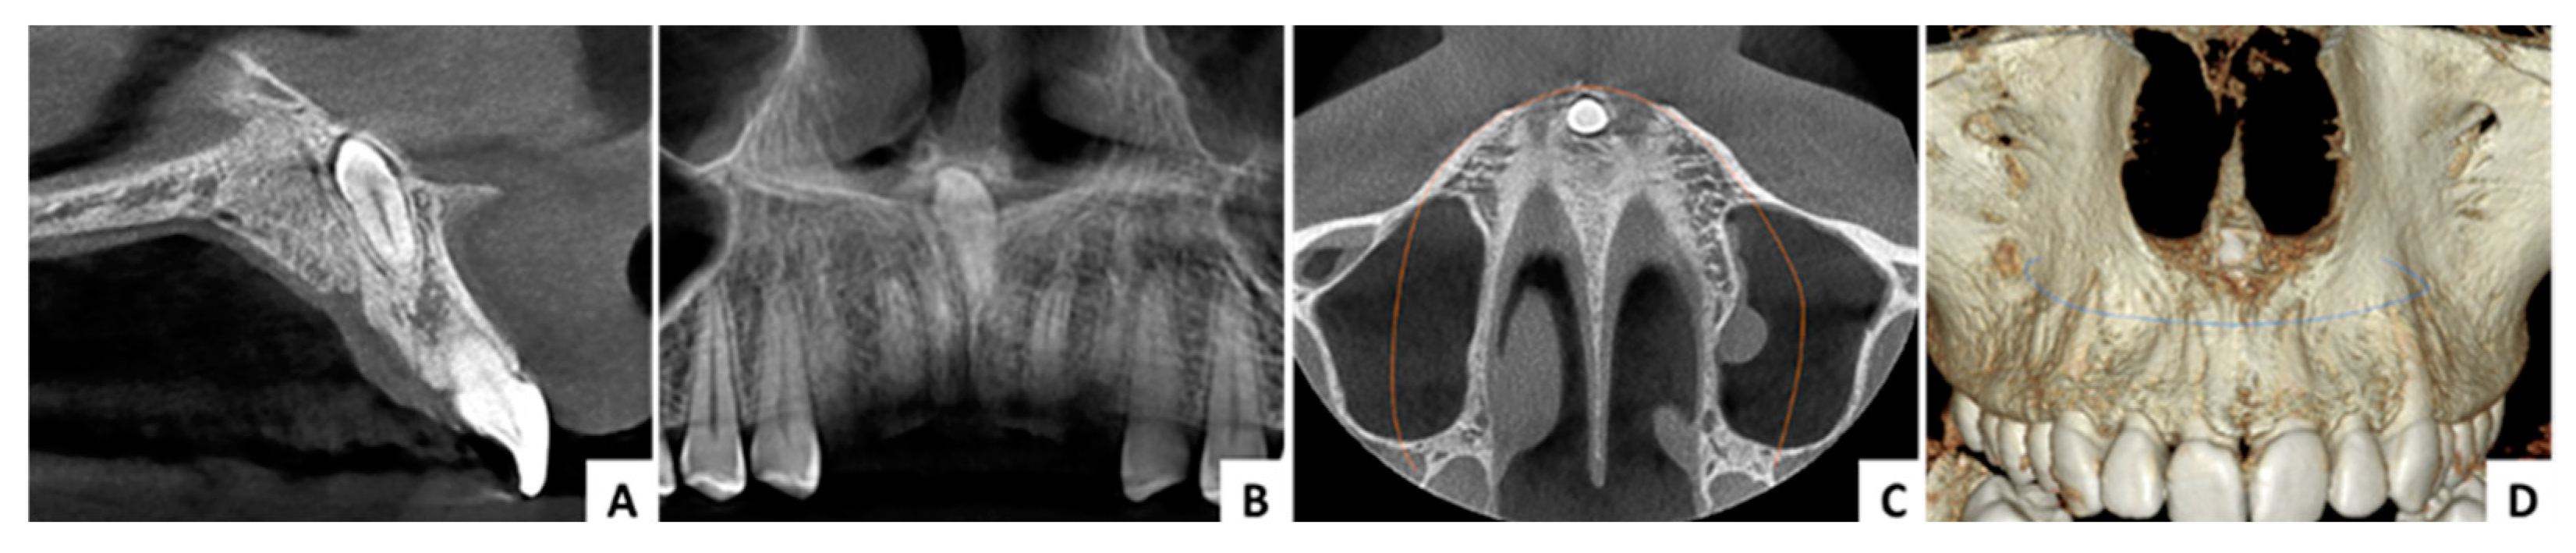

3.2. Case 2 (Figure 6, Figure 7 and Figure 8)

| Case No. | 1 | 2 | 3 |

|---|---|---|---|

| Age (years)/sex | 29/F | 11/M | 16/M |

| Angle formed by the mesiodens axis with the nasal floor | 85.93° | 143.5° | 144.4° |

| Distance from the ANS (mm) | 8.98 | 8.11 | 13.22 |

| Distance to mesiodens from buccal aspect (mm) | 4.71 | 3.70 | 3.84 |

| Distance to mesiodens from palatal aspect (mm) | 6.43 | 5.47 | 6.82 |

| Relation with nasal cavity | Covered with bone | Submucosally | Covered with bone |

| Position regarding nasopalatine canal | In front | In front | In front |

| Operation time (minutes) | 30 | 28 | 31 |

| Complications | No | No | No |